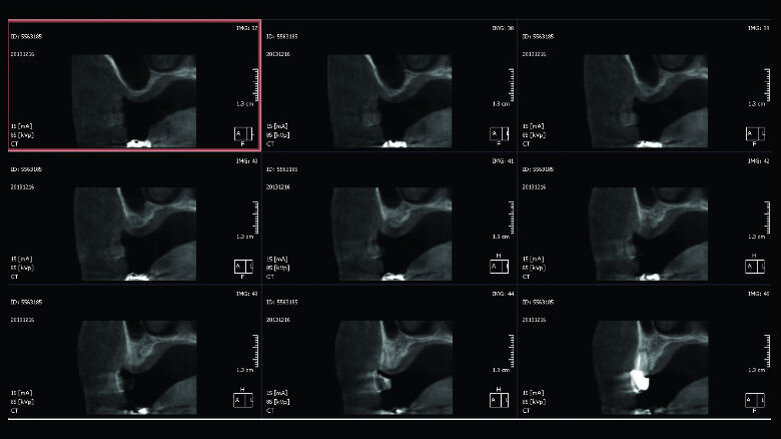

Paziente di sesso femminile, 48 anni, non fumatrice, si rivolge al nostro studio con la richiesta di ripristinare la normale masticazione, ostacolata dall’assenza di due denti precedentemente estratti. L’esame obiettivo evidenzia la mancanza di due elementi dentari nel primo quadrante (1.5 e 1.6). L’anamnesi della paziente è negativa, con un buon livello di igiene e un biotipo gengivale spesso. Viene pertanto prescritta una tomografia computerizzata, CBCT, per valutare il volume di osso disponibile per la riabilitazione (Fig. 1). Analizzando i risultati della CBCT si evince che l’osso basale non è sufficiente a stabilizzare gli impianti necessari per la riabilitazione implanto-protesica e appare ovvia l’esigenza di un aumento dei volumi dello stesso.

Di seguito viene valutata l’anatomia del seno mascellare, in particolare analizzando l’angolo tra la parete mediale e la parete laterale del seno, che ne determina l’ampiezza3. Vista l’assenza di setti e data la buona ampiezza del seno mascellare viene scelto un approccio per via laterale, in grado anche di consentire un miglior controllo dei volumi ossei innestati, considerando che gli impianti da inserire sono due. Si procede, quindi, con l’allestimento di un lembo a tutto spessore con tagli di scarico sia mesiale che distale (Figg. 2, 3) e a un’antrostomia per riflessione con bisturi piezoelettrico (Surgybone, Silfradent, Italia) (Fig. 4), che permette un miglior controllo dell’osteotomia4-5, riducendo il rischio di perforazione della membrana di Schneider.

Fig. 1_CBCT preoperatoria: si noti la mancanza di osso necessario a stabilizzare due impianti.